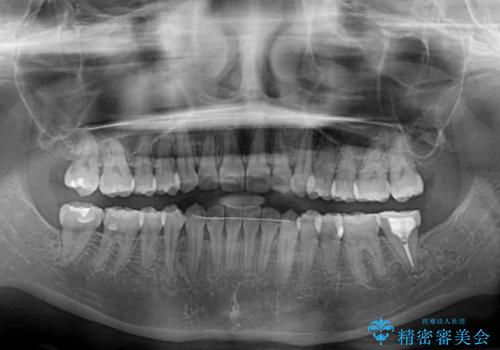

前歯のクロスバイト ワイヤー装置を併用したインビザライン矯正

- 前歯の捻転とクロスバイトが気になり、インビザラインによる矯正治療を希望して来院された患者様です。

上顎側切歯(上の真ん中から2番目の歯)が舌側転位している場合、インビザラインでは仕上げきれないことが多く、更には無理して動かそうとすると歯髄壊死を起こすリスクが高いと言われています。

インビザラインで歯列を移動する前に、上顎前歯をワイヤー矯正で整え、その後上下歯列をインビザラインにて矯正治療を行うこととしました。

舌側転位している側切歯特有の、切縁の位置が不揃いであったり、根元が内側に引っ込んだ状態であったりという、インビザライン独特の仕上がりになることなく、きれいに整った歯列とすることができました。